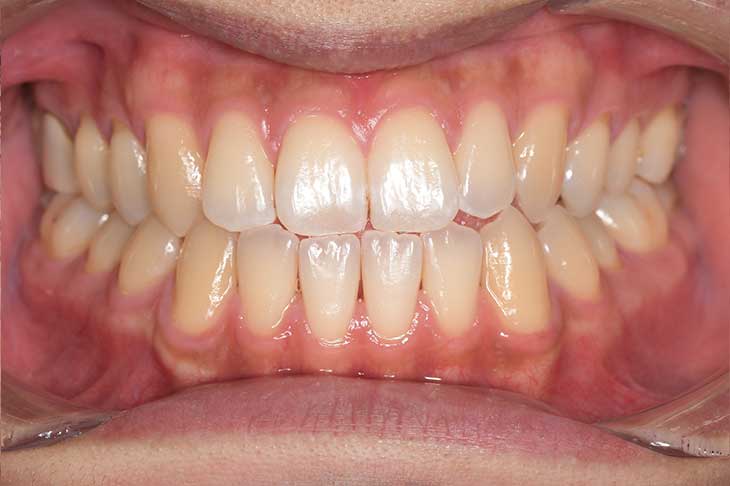

Before

After

| 主訴 | 見た目をきれいにしたい |

| 治療期間 | 6ヶ月 |

| 治療費 | ジルコニアボンド(セラミックの被せもの)¥165,000×7(税込み) オフィスホワイトニング4回 ¥4,400×4(税込み) ホームホワイトニング¥11,000 |

| リスク・副作用 | かみ合わせがとても強い方の場合、稀に割れてしまうことがあります。 |

| 先生からの提案 | 上の前歯6本と右下の2番目の歯はセラミックの被せもので治療。 残りの下の前歯5本はプラスチックの材料で虫歯を治療し、 ホワイトニングをおこないました。白くなったご自身の歯の色に合わせてセラミックの 被せものを作成しています。 模型上で完成後をシュミレーションし、上の歯茎の位置をきれいに見えるように 揃えています。(外科処置はしていません) |